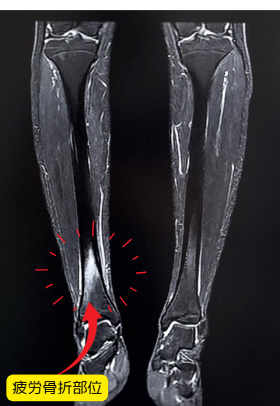

疲労骨折(ひろうこっせつ)

疲労骨折とは、同じ部位に繰り返し負荷がかかることで、骨に小さなひび(微細な骨折)が生じる状態です。

激しい運動や急激な練習量の増加、柔軟性の低下、筋力不足などが原因となります。

特に成長期のスポーツ選手や、体の使い方が未熟な初心者に多く見られます。

好発部位は脛骨(すねの骨)、中足骨(足の甲の骨)、腓骨、肋骨、腰椎(腰の疲労骨折)などでスポーツの種類によって異なります。

レントゲンやエコー、MRI、CTなどを用いて診断します。初期の段階では画像に写らないこともあるため、問診や圧痛の場所が診断の手がかりになります